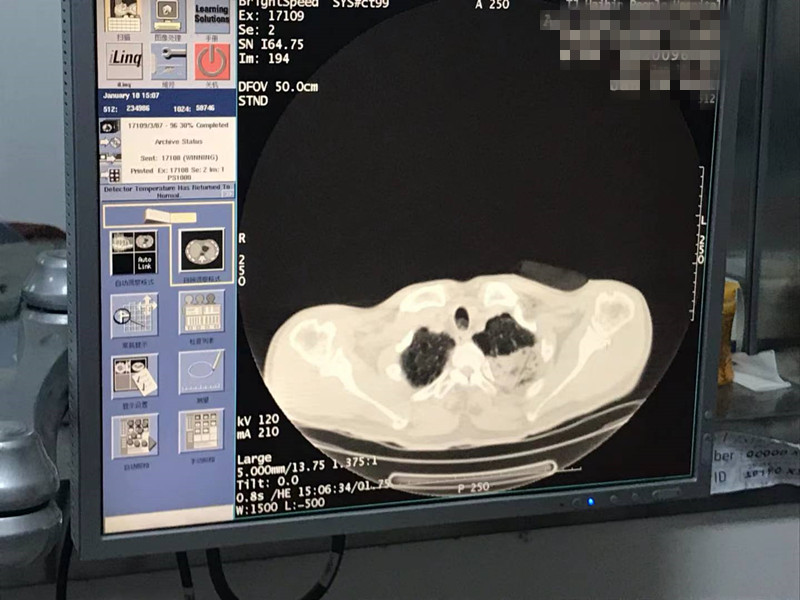

2021年1月份肺部氩氦刀手术